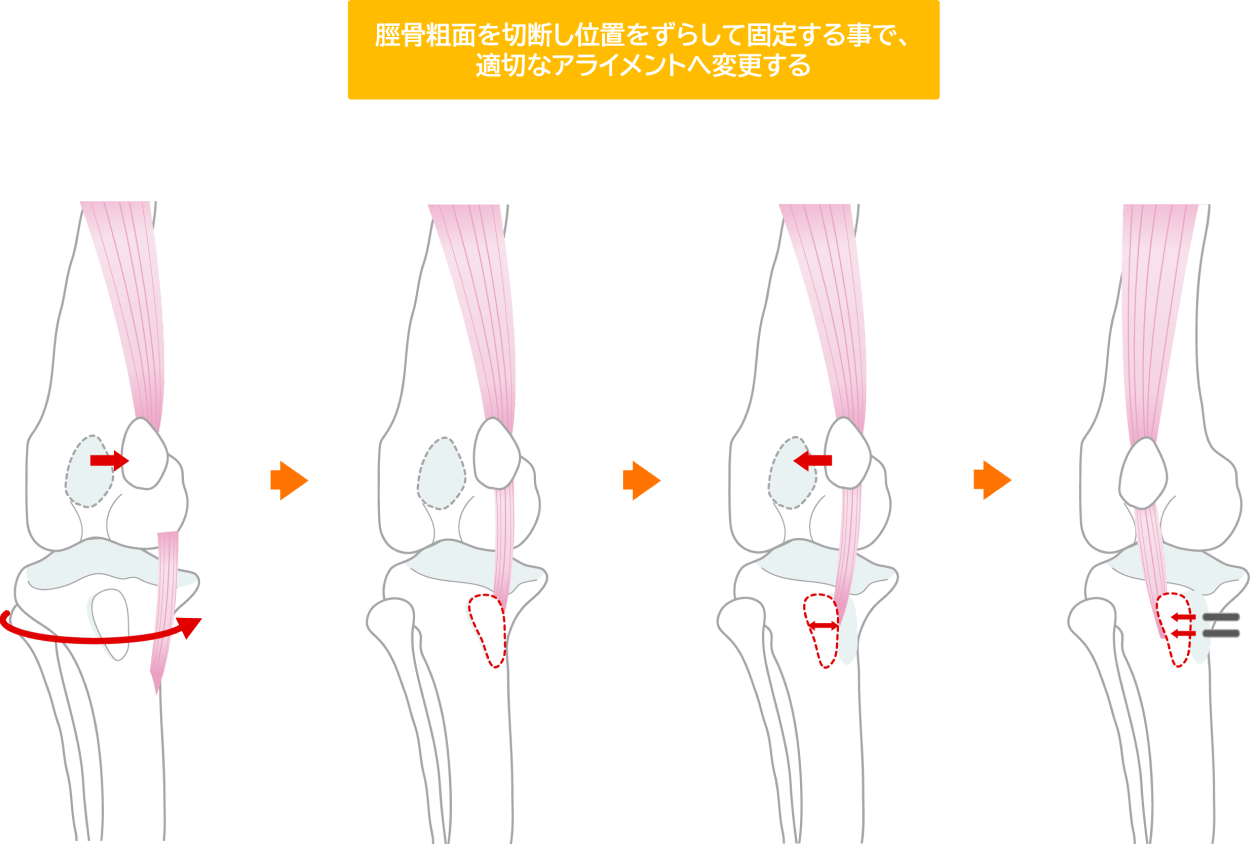

脛骨粗面転位術

脛骨の上部(脛骨粗面)を切り離し、適切な位置に移動させて固定します。これにより、膝蓋靭帯の付着部位を調整し、膝蓋骨にかかる力の方向を正常化します。

これらの手術法は、個々の症例の状態に応じて、単独または組み合わせて実施されます。術後は適切なリハビリテーションが重要で、専門的なケアにより良好な回復が期待できます。